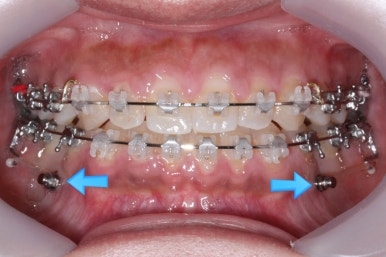

다음 단계는 작은 어금니 부위에 모아진 틈을 없애는 것입니다. 앞서도 말씀을 드렸듯이 앞니의 앞-두로의 위치는 변화 시키면 안되기 때문에 오로지 어금니를 앞으로 당겨오면서 틈을 모아줘야 합니다.

어금니를 100% 당겨주는 방법은?

바로 미니스크류 입니다. 위 사진에서 화살표 부분이 바로 미니스크류 입니다.

뼈에 단단히 고정해 놓고 어금니를 앞으로 당겨오는데 사용을 하게 됩니다. 교정치료 후에는 제거하게 되며 긍방 뼈가 차기 때문에 별로 걱정은 하지 않으셔도 됩니다.